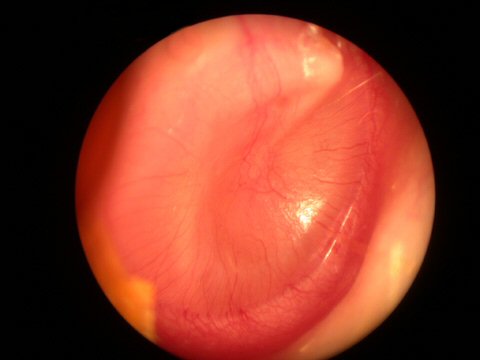

Notice the different shades of color yet the eardrum still remains an opaque translucent appearance in all the pictures